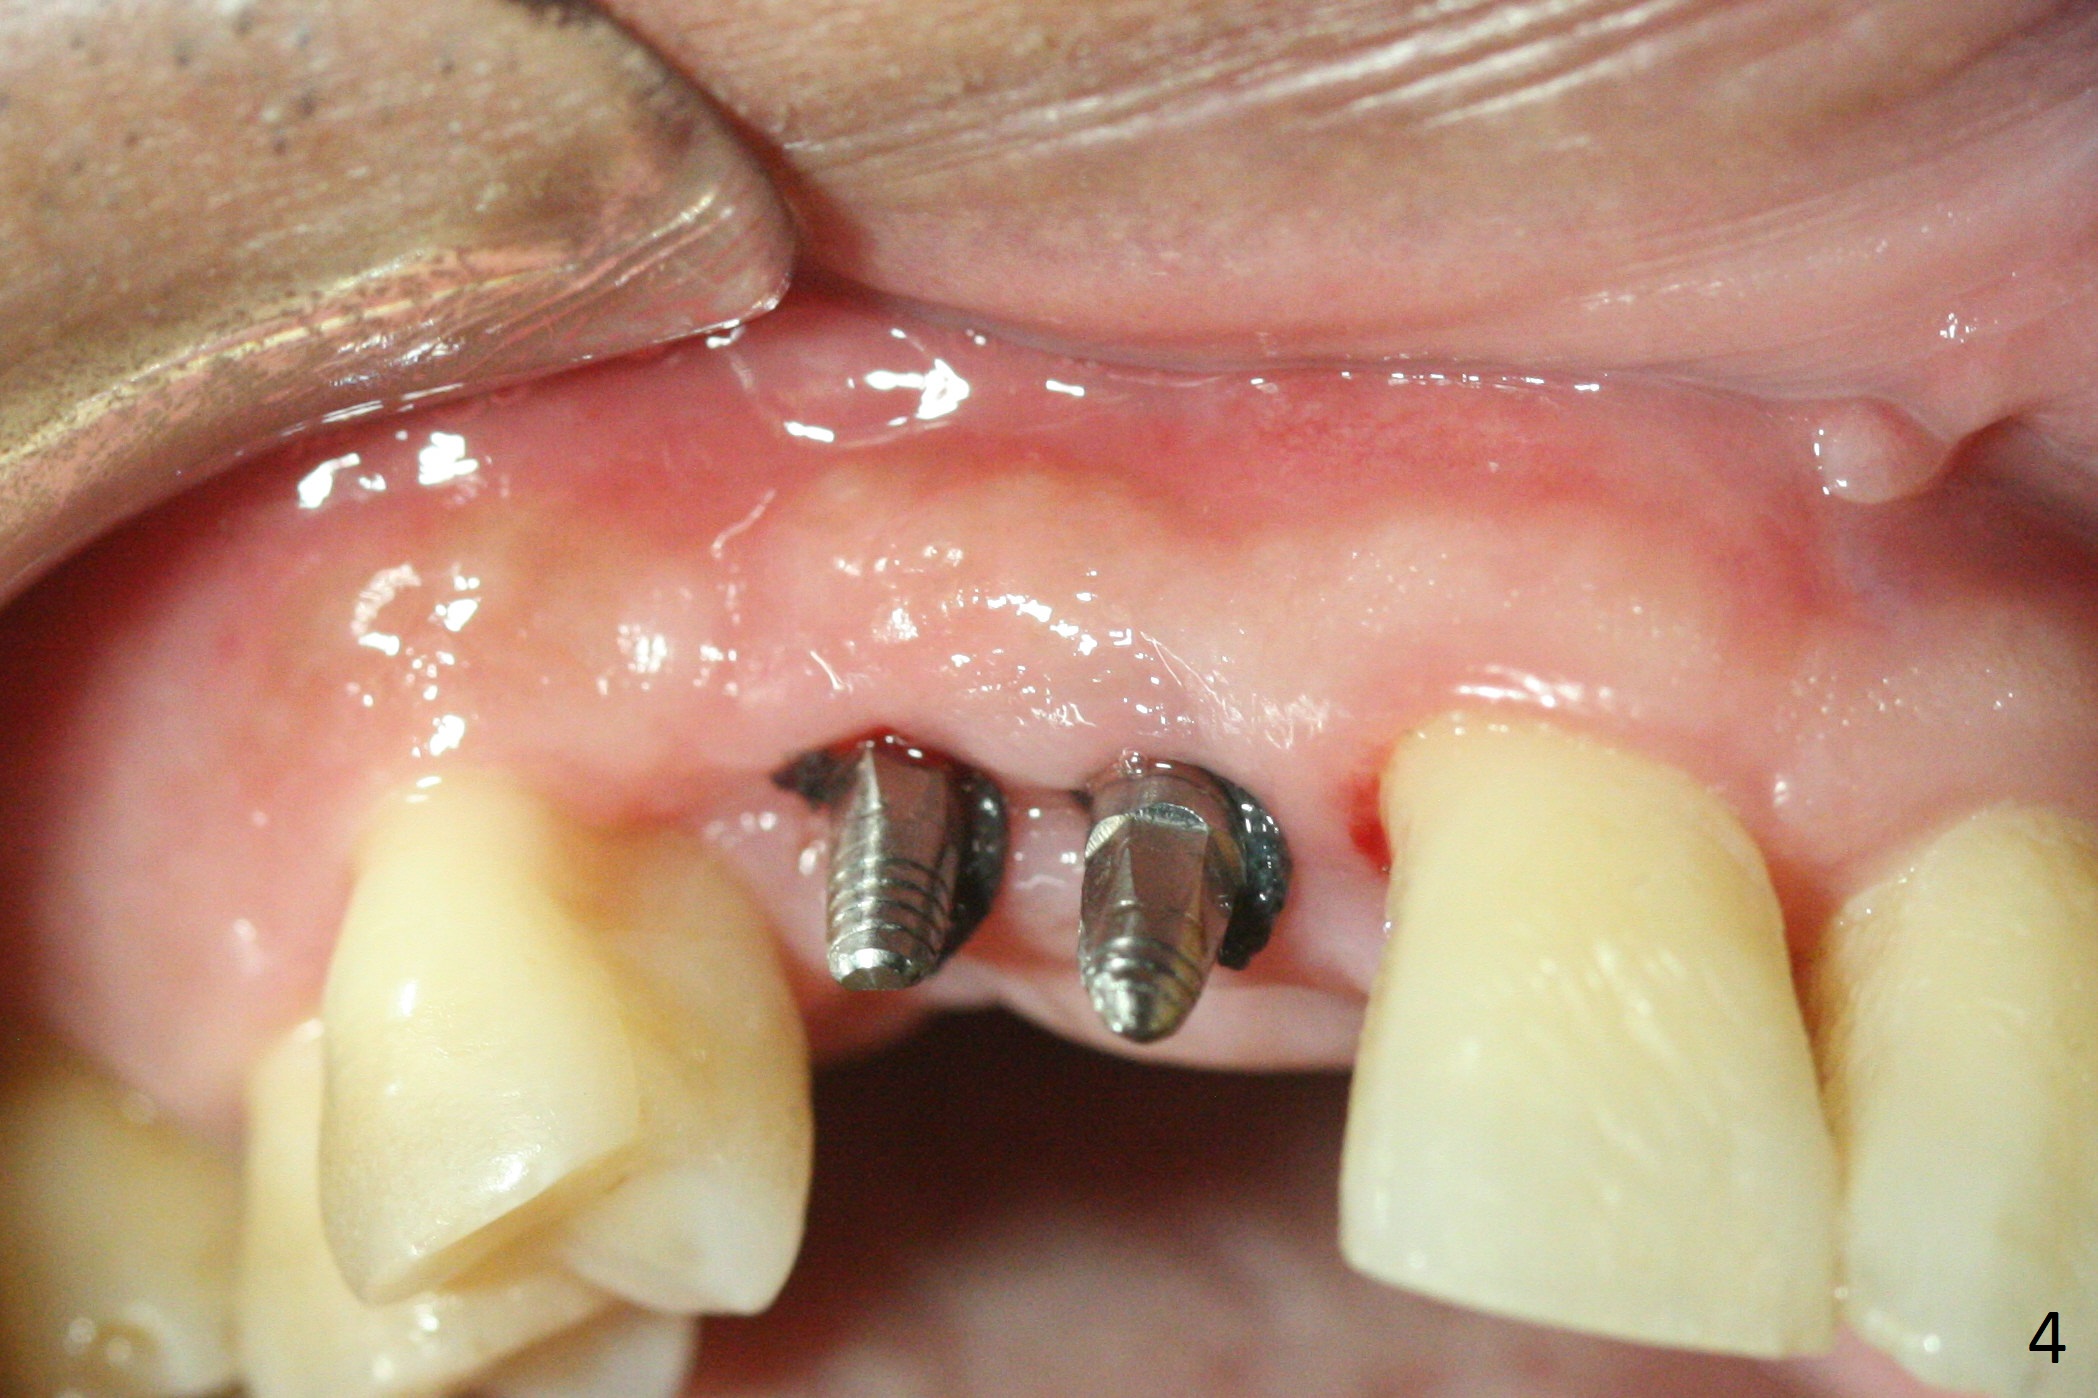

The ridge at the sites of #6 and 7 looks wide, but the bone is narrow (~ 4 mm) when the flaps are raised. Two of 3 mm 1-piece implants (3x16(2) and 3x14(4) mm) are placed (Fig.1,2). The other advantage of use of 1-piece implants is the narrow mesiodistal space. In fact the gingiva is wide and thick (4 mm). It is ideal to place implants with 4 mm cuff; unfortunately there is no 3x16(4) mm implant available at the site of #6. After adjustment of the abutment at #7, a splinted provisional is fabricated. Due to the shortness of the abutment at #6, definitive crowns may have to be splinted. Water Pik has been recommended.

There is no bone loss 3 months postop (Fig.3). After reprep (Fig.4), shades are selected for the final crowns (Fig.5). Before crown cementation at #6 and 7, the patient notes asymmetry with the teeth on the other side (Fig.6). Our concerns are the lack of the papilla distal to #6 (Fig.7 * (multiple modification of provisional needed)) and slight inflammation due to insufficient oral hygiene (^).